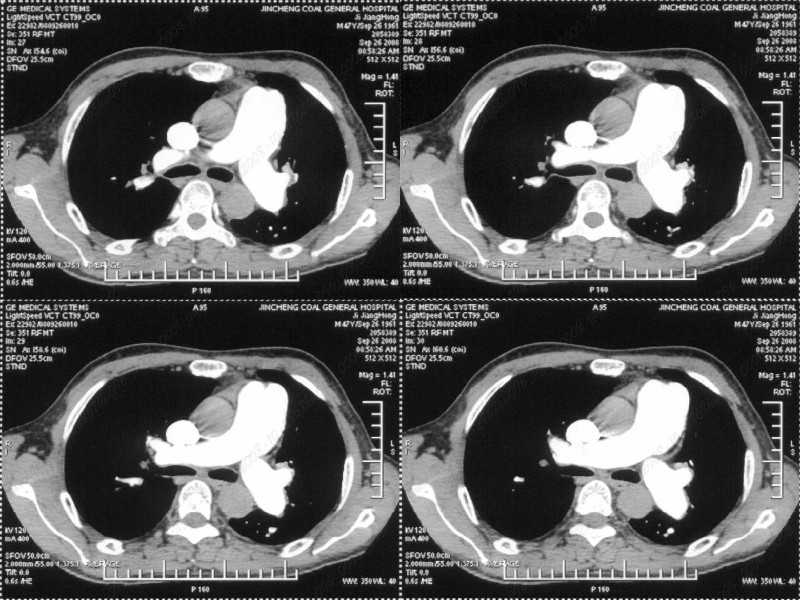

男性,47岁。胸部不适一年,ct检查发现右胸膜下结节。http://www.radida.com/bbs/forum.php?mod=viewthread&tid=46094

右下肺前胸膜下小结节,强化不明显。建议定期观察!

右肺中叶外侧段胸膜下结节状病灶,性质待定(不排除周围型肺癌可能)。

小结节的周围似乎与斜裂的走行有关,边缘分界不很清楚,与侧胸膜关系密切,有轻度强化,不能除外恶性,建议密切观察。